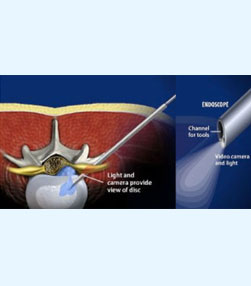

- Spine surgery - More than 3000 spinal surgeries including 40 spinal tumors microdiscectomy, MIS TLIF, artificial disc replacements, multilevel corpectomy, CV junction stabilization.

- Endoscopic brain surgeries - More than 300 endoscopic third ventriculostomies, 30 ventricular tumors.